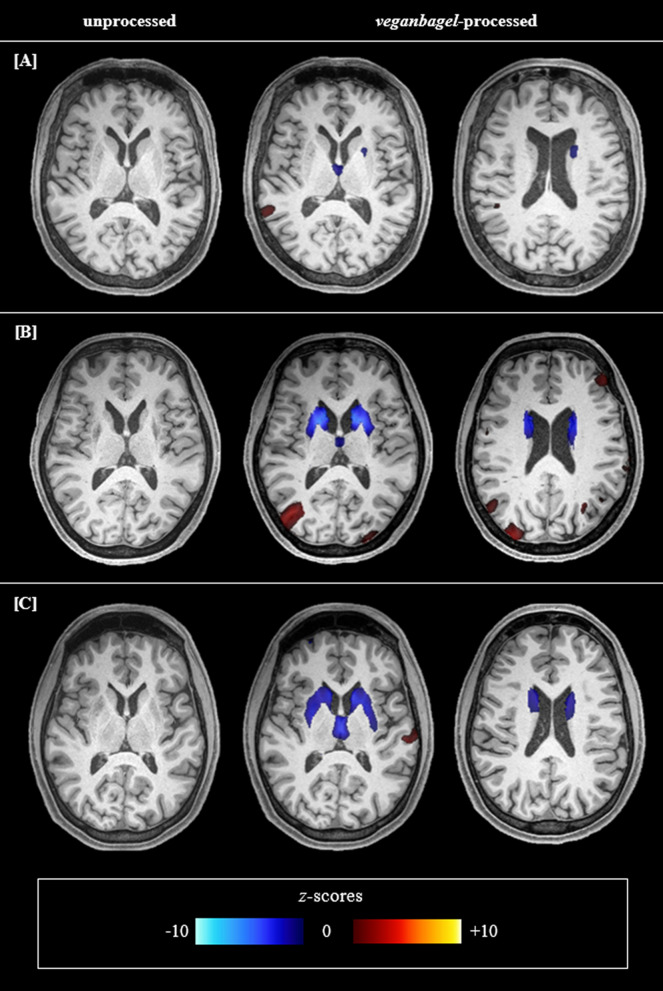

Methods: In this study, 30 WD patients and 30 age- and sex-matched healthy controls were enrolled prospectively and underwent structural magnetic resonance imaging (MRI). Regional atrophy was evaluated using established linear radiological measurements and the automated workflow volumetric estimation of gross atrophy and brain age longitudinally (veganbagel) for age- and sex-specific estimations of regional brain volume changes. Brain Age Gap Estimate (BrainAGE), defined as the discrepancy between machine learning predicted brain age from structural MRI and chronological age, was assessed using an established model. Atrophy markers and clinical scores were compared between 19 WD patients with a neurological phenotype (neuro-WD), 11 WD patients with a hepatic phenotype (hep-WD), and a healthy control group using Welch's ANOVA or Kruskal-Wallis test. Correlations between atrophy markers and neurological and neuropsychological scores were investigated using Spearman's correlation coefficients.

Results: Patients with neuro-WD demonstrated increased third ventricle width and bicaudate index, along with significant striatal-thalamic atrophy patterns that correlated with global cognitive function, mental processing speed, and verbal memory. Median BrainAGE was significantly higher in patients with neuro-WD (8.97 years, interquartile range [IQR] = 5.62-15.73) compared to those with hep-WD (4.72 years, IQR = 0.00-5.48) and healthy controls (0.46 years, IQR = - 4.11-4.24). Striatal-thalamic atrophy and BrainAGE were significantly correlated with neurological symptom severity.

Conclusions: Our findings indicate advanced predicted brain age and substantial striatal-thalamic atrophy patterns in patients with neuro-WD, which serve as promising neuroimaging biomarkers for neurological and cognitive functions in treated, chronic WD.